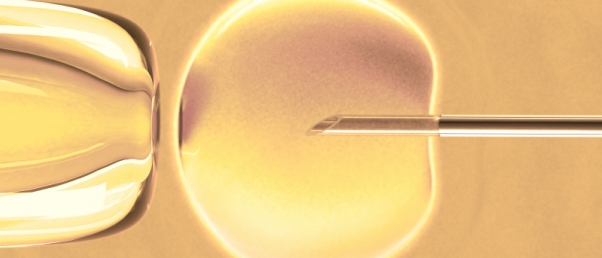

En Angleterre, les chiffres publiés par la « Human Fertilisation and Embryology Authority » (HFEA) font état de plus de 250 000 bébés nés par FIV depuis 1978. C’est ce que mentionne un département du ministère de la Santé britannique qui ajoute que le 250 000e bébé né par FIV a vu le jour en février 2015.

Par ailleurs, les chiffres du HFEA montrent une forte augmentation du nombre de FIV et des autres traitements de PMA depuis les 25 dernières années, avec un taux de réussite qui est passé de 14% en 1991 à 26,5% en 2014 (cf. Angleterre : les chiffres des FIV).

La British Fertility Society s’est félicitée de ces chiffres.Sally Cheshire, présidente de la HFEA, salue elle aussi la nouvelle : « Lorsque la HFEA a été créée en 1991, nous n’aurions jamais pu imaginer que plus de 250 000 bébés seraient nés seulement 25 ans plus tard grâce à la reproduction assistée ».

Susan Seenan, directrice générale de l’organisme de bienfaisance Charity Infertility temporise : « Un sondage récent souligne qu’au Royaume-Uni, si vous avez besoin de FIV, vous devez faire face à une série d’obstacles émotionnels, sociaux et financiers. Il faut payer des sommes astronomiques, ne pas recevoir d’informations médicales appropriées, ne pas avoir de soutien psychologique, et voir parfois ses relations sociales se détériorer. Il reste beaucoup à faire pour aider les individus touchés par les problèmes de fertilité. (…) La FIV ne convient pas à tout le monde ».